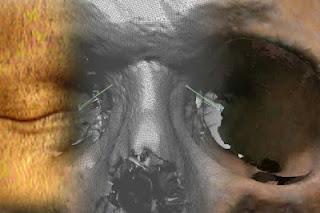

Hasta ahora, los puntos de referencia que se tienen en cuenta para analizar un cráneo no se corresponden totalmente con los de la piel o los ojos, lo que dificulta saber cómo eran los individuos cuando estaban vivos. Navarro Merino utilizó una muestra de 500 personas de origen mediterráneo, haciendo tomografías en 3D y comparando los puntos de los huesos craneales con los de los rostros.

Descubrió así que la relación entre ellos no era perpendicular, como se ha pensado hasta ahora, sino en ángulo. "Son esos vectores, su dirección, sentido y distancia, los que dan fiabilidad a las mediciones", explica a ELMUNDO.es.

Los 500 participantes se escogieron de una muestra de estudios tomográficos (TAC) de los hospitales de Castilla-La Mancha, con los que tiene un acuerdo la Universidad de Granada. Los científicos crearon una base de datos con las coordenadas en 3D tanto de los puntos craneales como los faciales y obtuvieron los vectores.

Para ver si la técnica funcionaba, hicieron un escáner en 3D del cráneo de un indiviudo fallecido y crearon un modelo virtual sobre el que localizaron y marcaron todos los puntos craneales (craneométricos), haciendo lo mismo en la fotografía de esta misma persona que facilitó la familia.